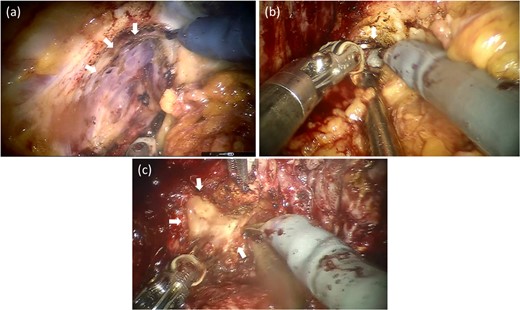

The operation findings and technics were followed (Fig. 4). The surgery was performed using the intra-abdominal approach. After dividing the Retzius space and the fat tissue in front of the prostate, bilateral endopelvic fascia incisions were made. The right endopelvic fascia had moderate adhesions, and the left endopelvic fascia presented with strong adhesions (Fig. 4a). The vesico-prostatic junction was divided with the lateral approach. The retrotrigonal layer was easily identified from the right side. However, the left side had an extremely strong adhesion and could not be identified (Fig. 4b). Finally, bladder neck sparing was conducted from the right side without bladder neck reconstruction. Extremely strong adhesions around the bilateral ampulla of the vas deferens and the back of the prostate were observed, which were the most difficult points in this surgery. Nonetheless, the prostate was ultimately removed without major intraoperative issues (Fig. 4c).

Operative findings after salvage robotic-assisted radical prostatectomy. The left endopelvic fascia had a strong adhesion to the levator ani and was challenging to divide (a). The retrotrigonal layer forming the left side had an extremely strong adhesion and could not be identified (b). The back part of the prostate had the strongest adhesions. The left ampulla of the vas deferens was almost dissolved and could not be identified (c).